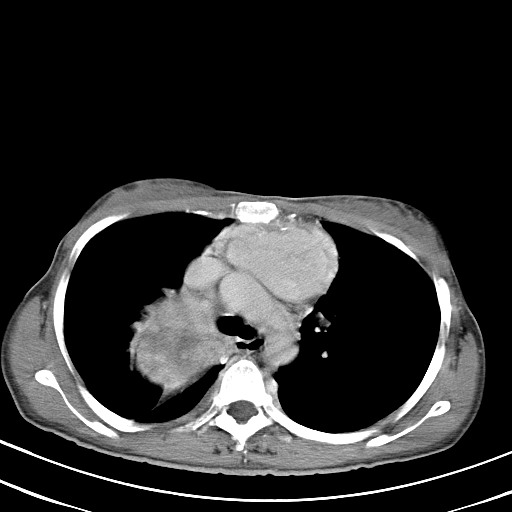

以下是引用汪涛同志在2007-8-2 0:40:00的发言:[br]病变虽然广泛,同时侵及双侧纵隔,但是无论左侧和右侧上下观察都是与右侧颈部甲状腺相延续的,而且强化幅度基本一致,又同时具有恶性病变病变的某些特征:肿块过大且密度不均,部分层面与正常纵隔结构分界不清,结合病史已有两年,考虑:胸内甲状腺肿恶变可能。[br]